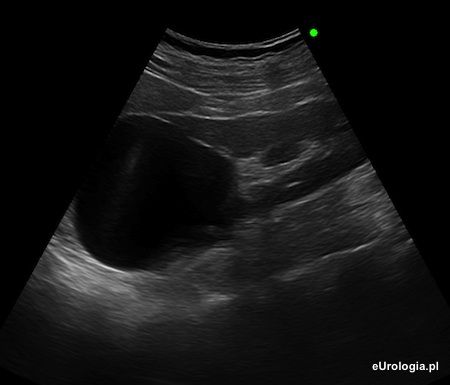

Fot. Torbiel prosta średnicy 57 mm w okolicy górnego bieguna lewej nerki - obraz w badaniu USG.

Torbiele proste nerek występują u blisko 30% populacji. Torbielą prostą nazywa się cienkościenną przestrzeń płynową wypełnioną jednorodnym płynem. Podstawową metodą diagnostyczną w przypadku torbieli nerek jest badanie USG. W przypadkach wątpliwych lekarz może zdecydować o wykonaniu tomografii komputerowej lub rezonansu magnetycznego - podejrzenie nieprawidłowości w świetle torbieli.

Torbiele proste nerek mogą mieć wielkość od kilku milimetrów do kilkunastu centymetrów i w większości przypadków nie wymagają żadnego leczenia. Wśród najczęstszych wskazań do wykonania punkcji torbieli wymienia się: ból lub uczucie ucisku spowodowane dużą objętością torbieli, zakażenie treści wewnątrz torbieli, dolegliwości kolkowe spowodowane uciskiem torbieli na moczowód, nadciśnienie tętnicze spowodowane niekorzystną lokalizacją torbieli. Więcej informacji można znaleźć w artykule: Torbiel nerki oraz Klasyfikacja Bosniaka torbieli nerek.